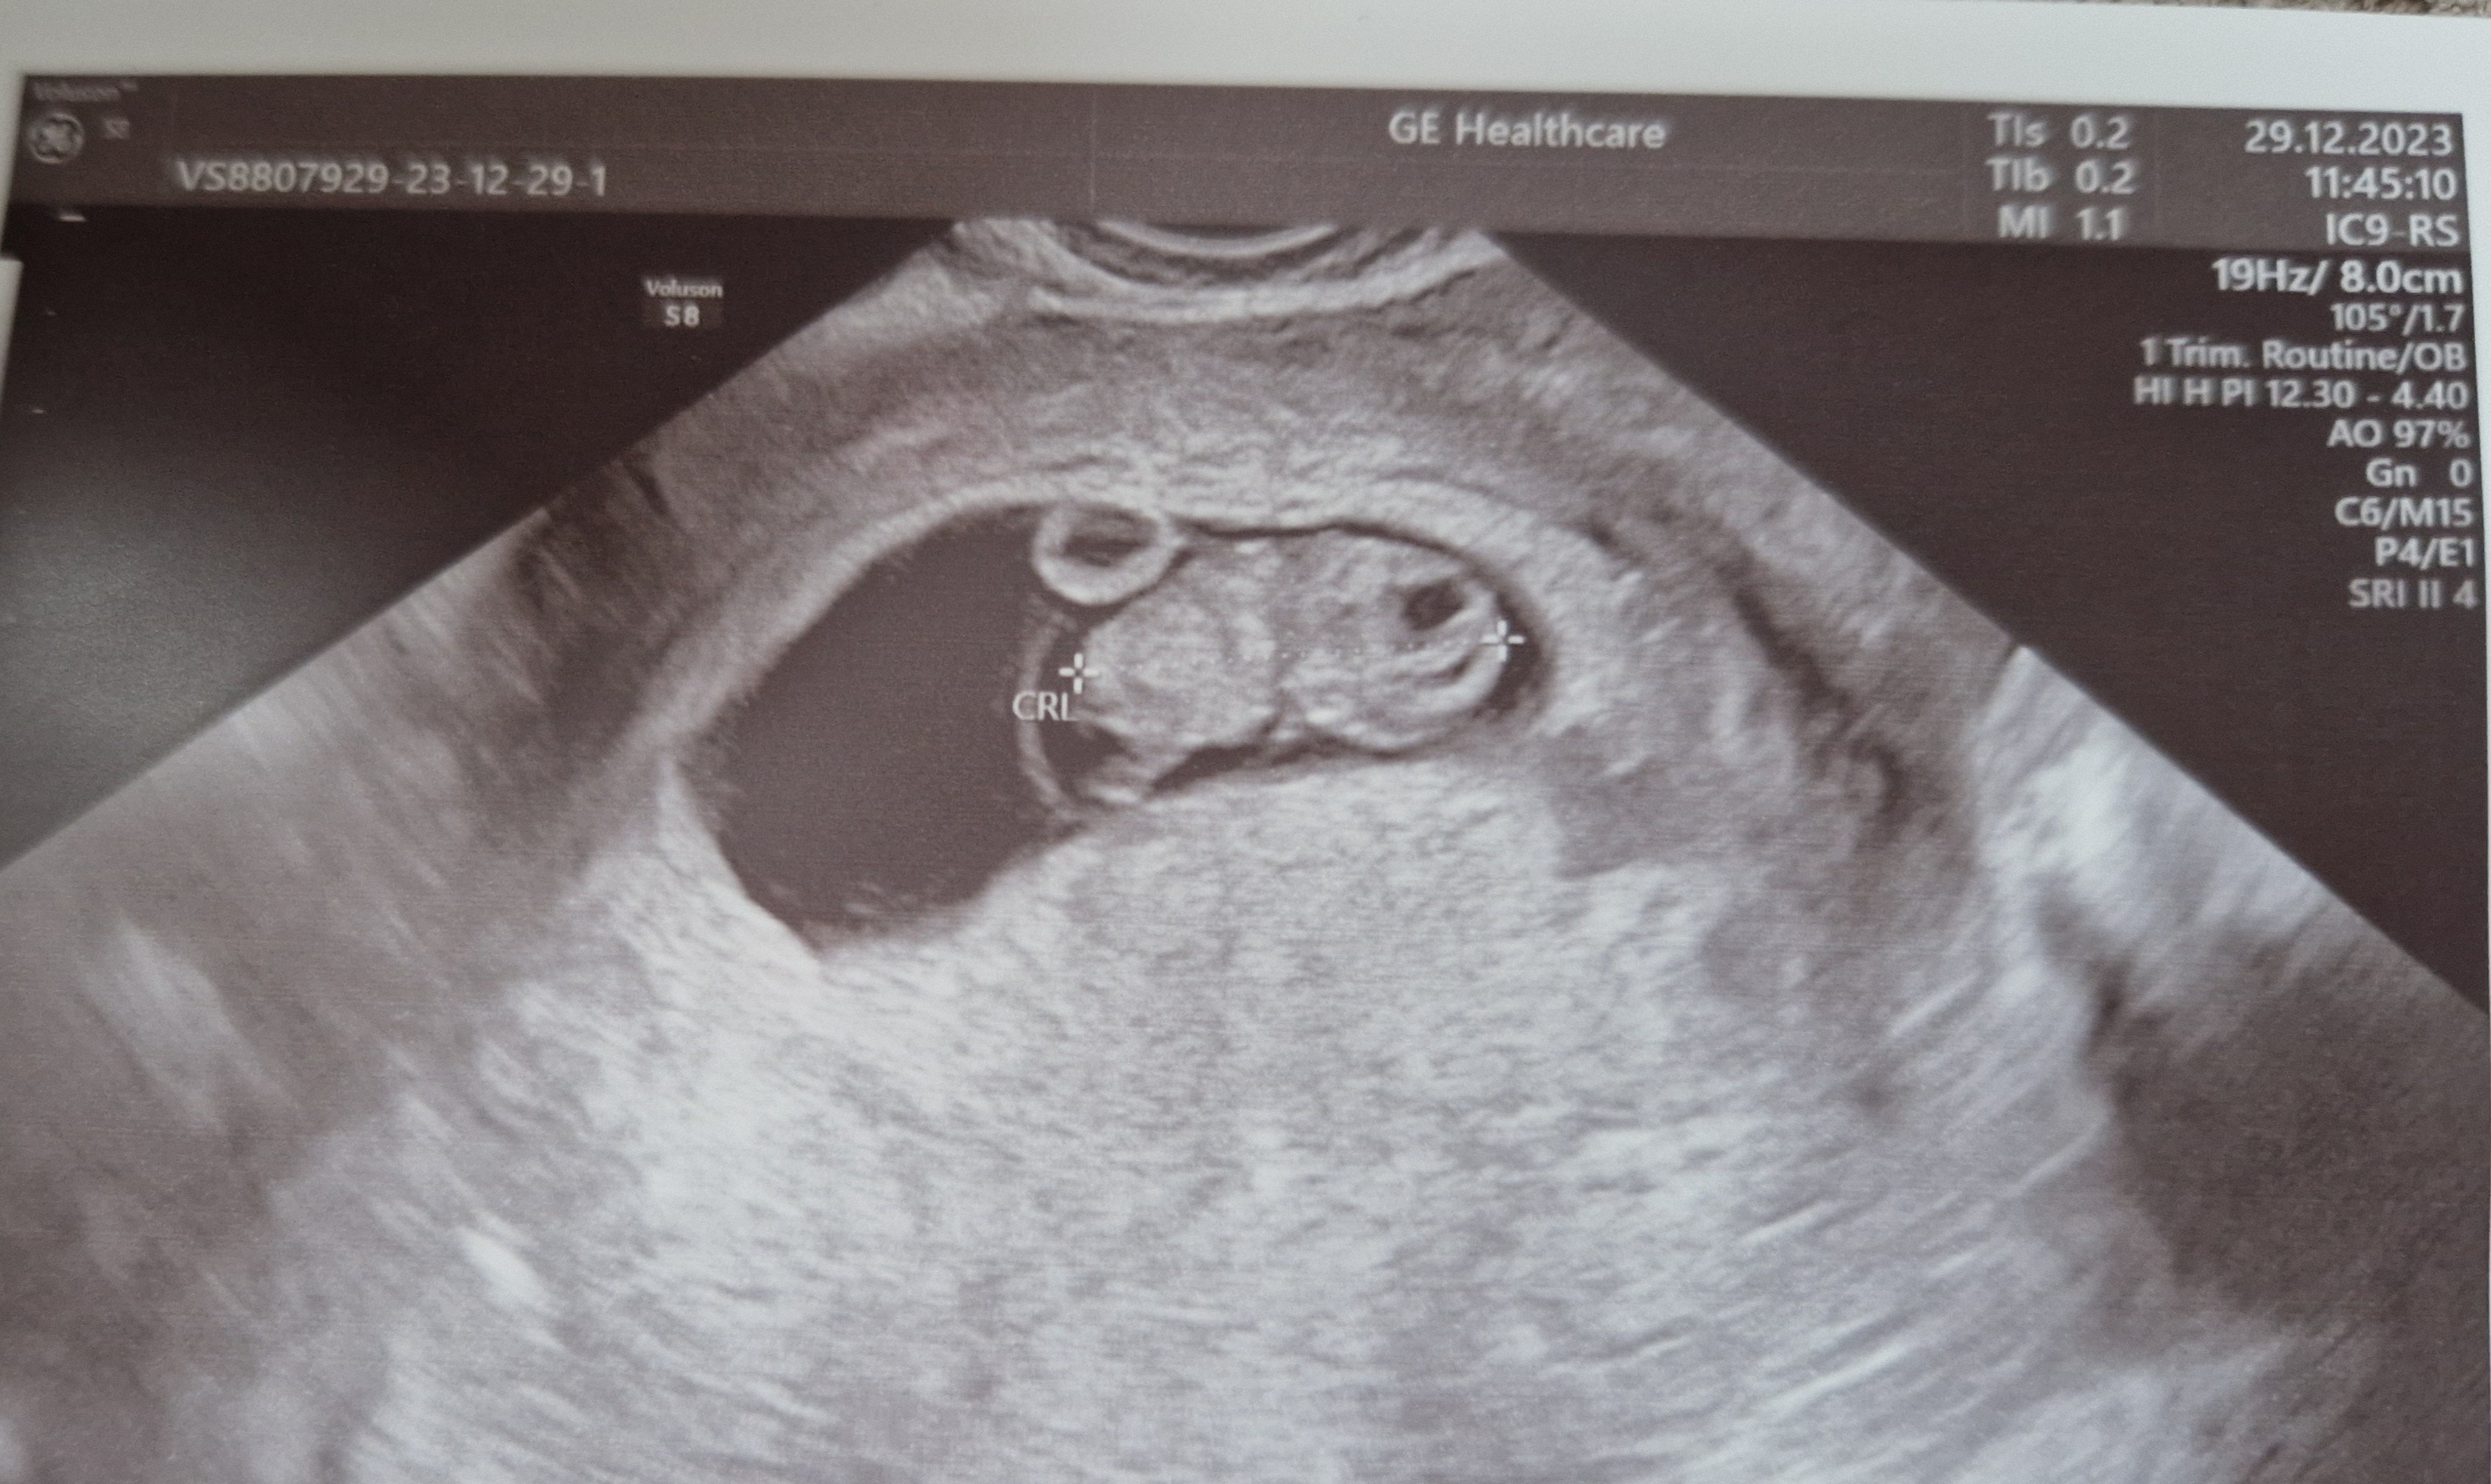

Wszystko super. 1.92 cm człowieczka, serce bije. Fajnie było widać już nóżki i pani doktor się śmiała, że jaki fajny już Kajtek xD

Zobacz załącznik 1598816